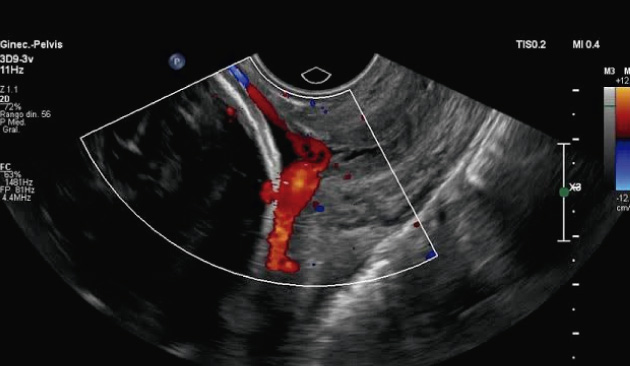

Expertos en detección temprana de anomalías. Brindamos una gama completa de Ultrasonidos Fetales y Ecografías 7D:

Viabilidad, Genética, Morfológica, Crecimiento Doppler, Ecocardiografía fetal, Neurosonografía fetal, etc.